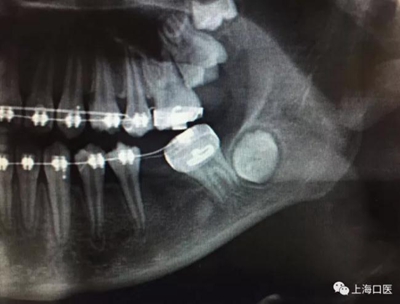

這是上海武廣增正畸工作室接診的一例非常規(guī)拔牙矯治病例,患者女性,初診年齡14歲。LL6殘冠拔除。LL7近中平移取代LL6,我們上傳了該患者一組下頜磨牙近中平移連續(xù)矯治過程的正畸X線片,與正畸界朋友分享。

來源:武廣增 上??卺t(yī)